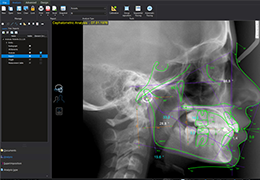

ANYTHINK 经导管主动脉瓣膜置换术分析系统